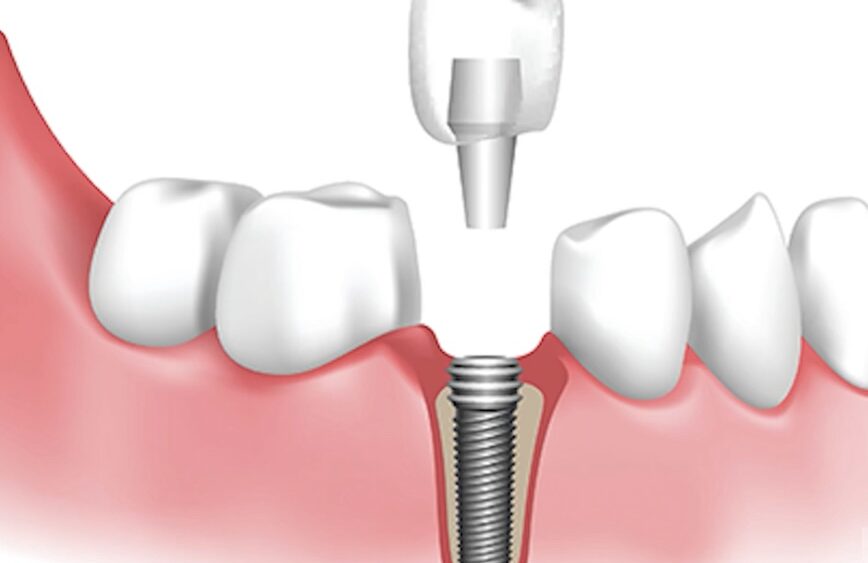

Dr. David Doman is back with another episode of Housecall, welcoming local periodontist Dr. Israel Puterman to the show. Puterman explains the difference between crowns, bridges, and implants, and details the dental implant process. Watch to learn everything you need to know about this increasingly common dental need.